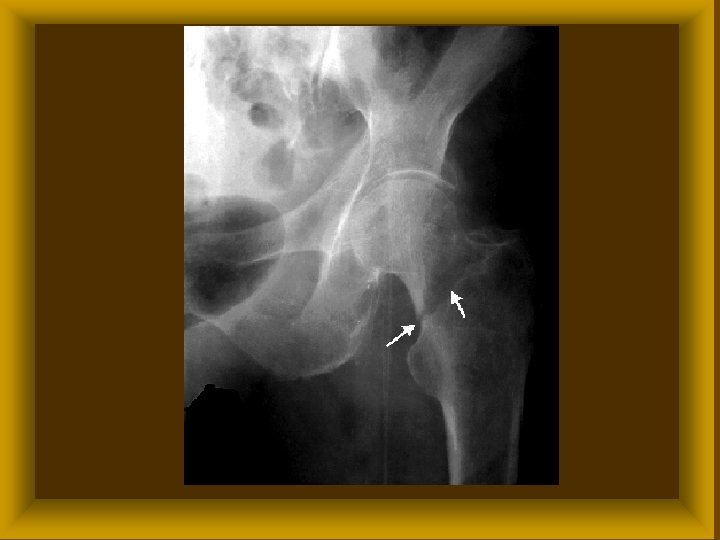

FICAM ( LUXATIO ) Ø Luxatio completa ( teljes ) Ø Subluxatio ( részleges ) Ø Veleszületett (csípőficam) Ø Szerzett * traumás * habituális * recidiv

Subluxatio

FICAM ( LUXATIO ) SZÖVŐDMÉNYEI ØIzületi tok, izmok szakadása ØBőr, ideg, érsérülések ØCsonttörés

FICAM ( LUXATIO ) TÜNETEI Ø Szubjektív fájdalom * működési zavar Ø Objektív * alakváltozás * rugalmas rögzítettség *

FICAM ( LUXATIO ) KEZELÉSE Ø Repositio ( narkózisban ) * konzervativ * műtéti Ø Rögzítés Ø Rehabilitatio